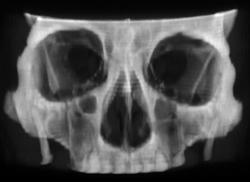

Diagnosis

Right Hip Dislocation